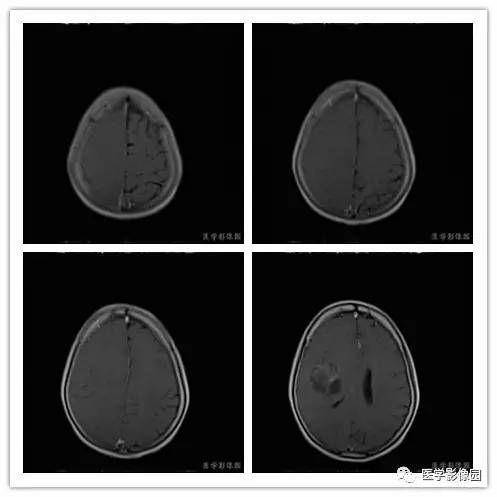

影像学表现:右侧颞叶深部区见一长T1、长T2囊样信号,成明显环形强化、未见明确结节影,没有FLAIR和DWI图,内见分隔,边界较清,周围水肿不明显,右侧脑室明显受压、颞角扩大,右侧脑沟明显变浅,脑中线结果向左偏移。

1.肿瘤主要表现为等长T1 、等长T2 混杂信号影,偶可见短T1 或短T2 信号影,注药后,肿瘤增强明显但不均匀;

4.肿瘤内常可见血管流空影而见不到钙化影;

5.肿瘤附近骨质可见破坏而见不到增生硬化。